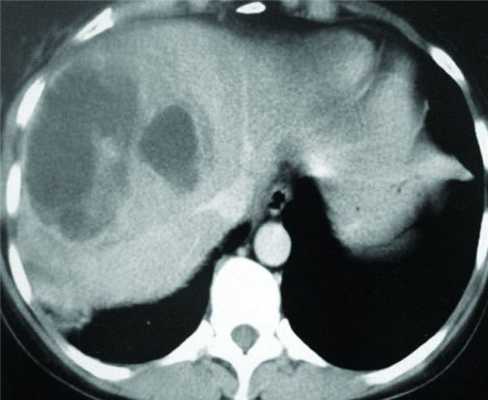

КТ-исследование абсцесса малого таза: Визуализация и диагностика